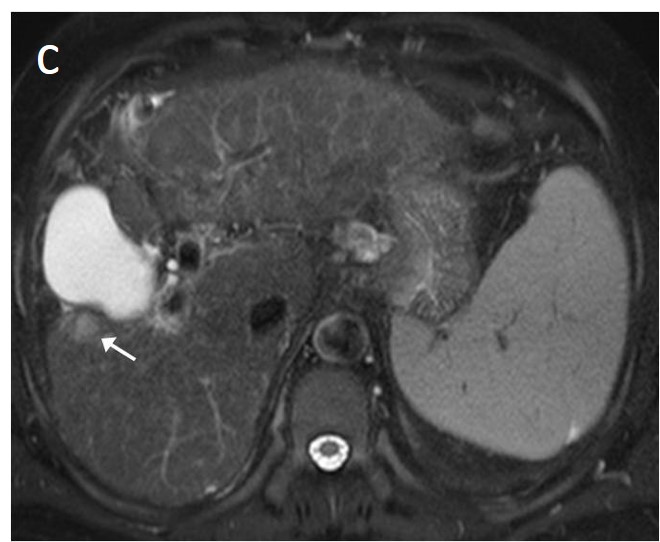

The presence of a capsule (Figure 12) is a major finding according to LI-RADS, but not EASL. The capsule is a characteristic feature of progressed HCC and is absent in dysplastic nodules or early HCCs. It shows low T1 and T2 signal intensity and enhancements on the portal and delayed phase at 3 min after contrast injection (or transitional phase if hepatospecific contrast agent is used); on the contrary, corona enhancement occurs earlier on the arterial phase. A capsule should be thicker than the fibrous septa of cirrhosis, which also show delayed enhancement. An intact capsule on imaging has been associated with lower recurrence rates after treatment [137], while extracapsular tumor extension predicts poor survival [138]. It should be stressed, however, that an encapsulated progressed HCC has a worse prognosis than an unencapsulated early HCC; the presence of a capsule confers a better prognosis only when the encapsulated tumor is compared to HCCs of a similar size and grade with breached capsules or without a capsule.

Figure 12. A large HCC is depicted in the right liver lobe of this 81-year-old man. The tumor is surrounded by a capsule, nicely seen as a thin, low signal line on the fat-suppressed T2 sequence (arrowheads) (a) and shows inhomogeneous but predominantly high T2 signal intensity. Areas of fat are clearly shown in the in/out of phase images (asterisk) (b,c). This marked heterogeneity is known as the “mosaic” pattern. After contrast administration, mottled arterial enhancement is noted (d); definite wash-out and capsular enhancement (arrows) are seen on the portal phase (e).

Fatty change is encountered in approximately 40% of early HCCs [143]. With increasing tumor size and histologic grade, fat usually regresses and the percentage drops to 6% in moderately-differentiated HCCs [144], only to increase again in highly de-differentiated tumors. This occurs along with the diminished arterial supply, suggesting a connection between reduced blood flow, hypoxia, and steatogenesis [145]. MRI is superior to CT in detecting fatty change with the use of chemical shift sequences, which show the characteristic signal drop on the opposed-phase compared to the in-phase (Figures 12 and 13). Intratumoral fat can also be used to exclude cholangiocarcinoma, which is also associated with cirrhosis. Nevertheless, the added value of fat identification in a HCC is debatable because, when detected, other more suggestive features (like the vascular pattern) are already present [123].

When a smaller nodule is seen within a larger nodule, it implies de-differentiation of a cell subpopulation and progression towards hepatocarcinogenesis. The “nodule-in-nodule” sign suggests development of HCC within a dysplastic nodule (Figure 13) and the typical HCC features, such as the wash-in/wash-out pattern or diffusion restriction, are seen in the inner nodule. When numerous foci with different imaging characteristics are seen within a nodule, the appearance is known as a “mosaic” pattern and is usually encountered in large tumors (Figure 12), thereby facilitating the differentiation from cholangiocarcinoma [54].